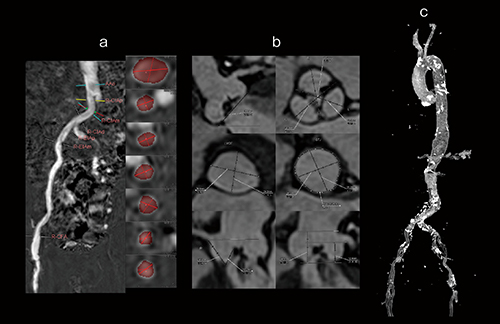

図2 非造影MRIによるTAVI術前評価

血清クレアチニン2.72mg/dL、eGFR 18.7mL/min/1.73m2と腎機能が悪く、造影CTが困難であった症例。アプローチサイトの計測(a)、弁周辺情報の計測(b)、石灰化の評価(c:非造影MRA+単純CTのフュージョン)で、TAVIに必要な項目が非造影MRIで得られる。